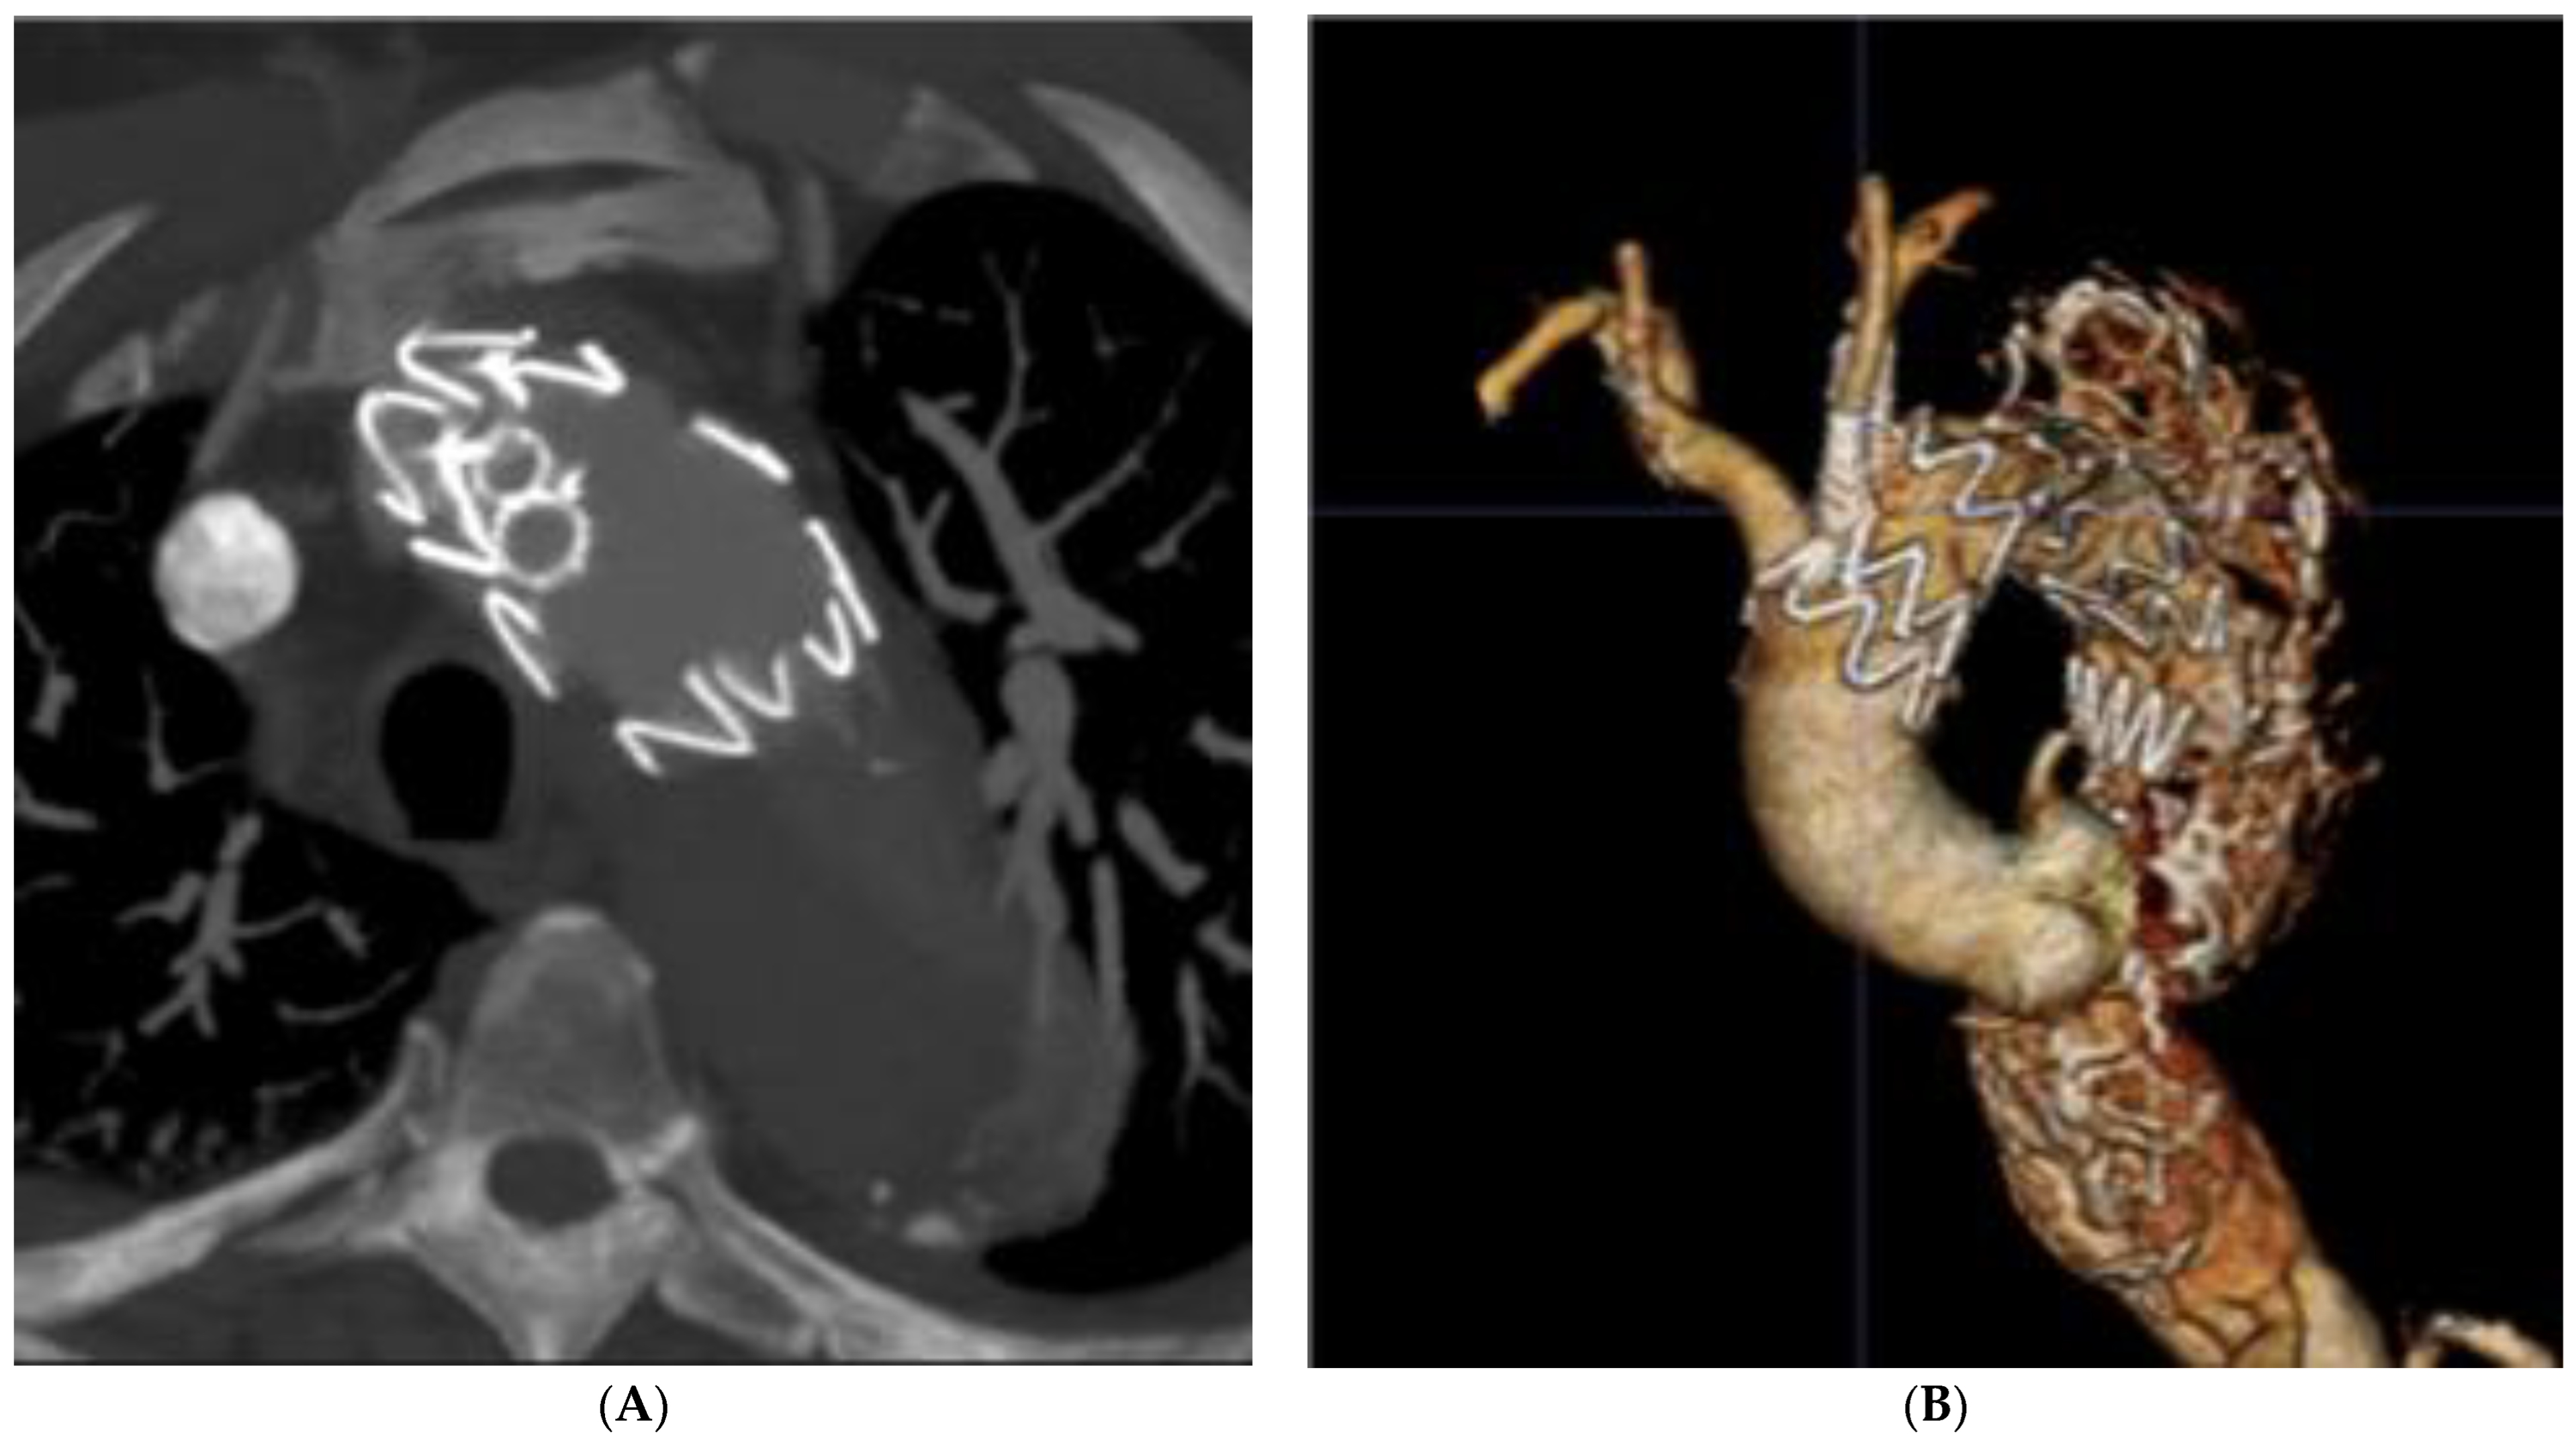

To compensate for the angulation between the greater curvature and the target vessel, an additional 6 or 7Fr JR4 or IM guide-catheter is recommended to facilitate the orientation of the coaxial system to the surface of the aortic graft. The use of a steerable catheter can also be considered. Once the guide-catheter is in contact with the fabric of the endograft, it is essential to verify its correct positioning. This is an essential step before activating the laser probe. The distal end of the guide-catheter must be positioned at the top of the “dome” of the TEVAR, pointing to the aortic center lumen. For this purpose, it is recommended to check its position on two orthogonal planes intersecting at the ostium of the target artery (Figure 2 and Figure 3). If there is too much angulation between the target artery and the greater aortic curvature, there is a risk of failed fenestration. In this setting, the laser probe often slips between the TEVAR and the anterior aortic wall.

Concerning the choice of the laser probe, previous studies have reported the use of the Spectranetics Turbo-Elite coronary atherectomy probe, which exists in several diameters from 0.9 to 2.5 mm, compatible with 0.014″ to 0.035″ guidewires. Progressive dilatation with coronary and non-compliant balloons is necessary to enlarge the fenestration while the use of cutting balloons can facilitate the passage of larger diameter balloons. Finally, balloon-expandable covered stents are better adapted to provide adequate sealing at the level of the fabric tear and into the target vessel (Figure 4).

Figure 4. Post-operative CT scan 3D volume rendering (A) of the in situ laser fenestrations of the left common carotid and left subclavian arteries. The 3D reconstruction (B) shows fenestrations position and patency.